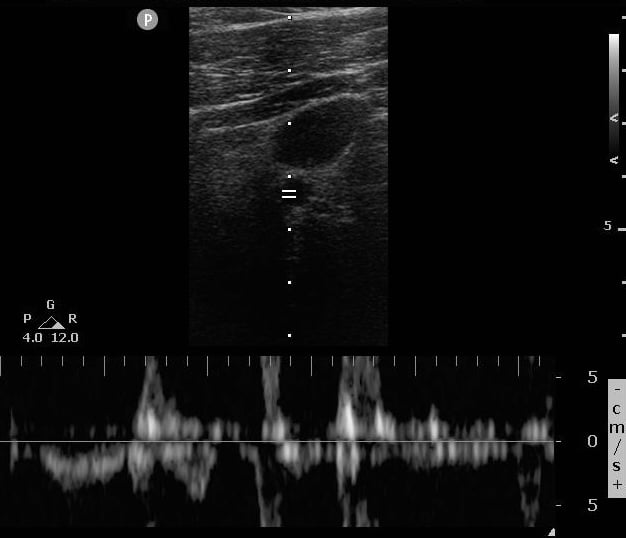

Case 1, Image 2.

Sustained regular Doppler pulsations during the pause, indicated ROSC. Image courtesy of Yale School of Medicine, Emergency Department.